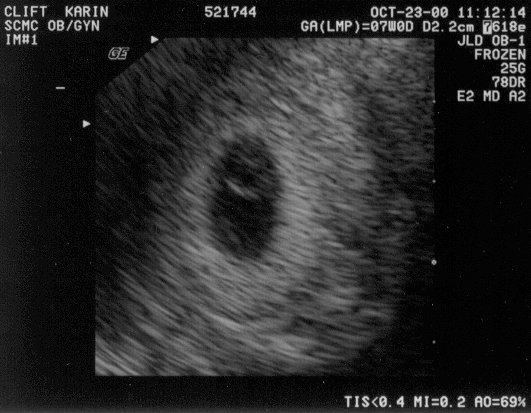

October 23 Saw the heart beating on ultrasound #1, #2